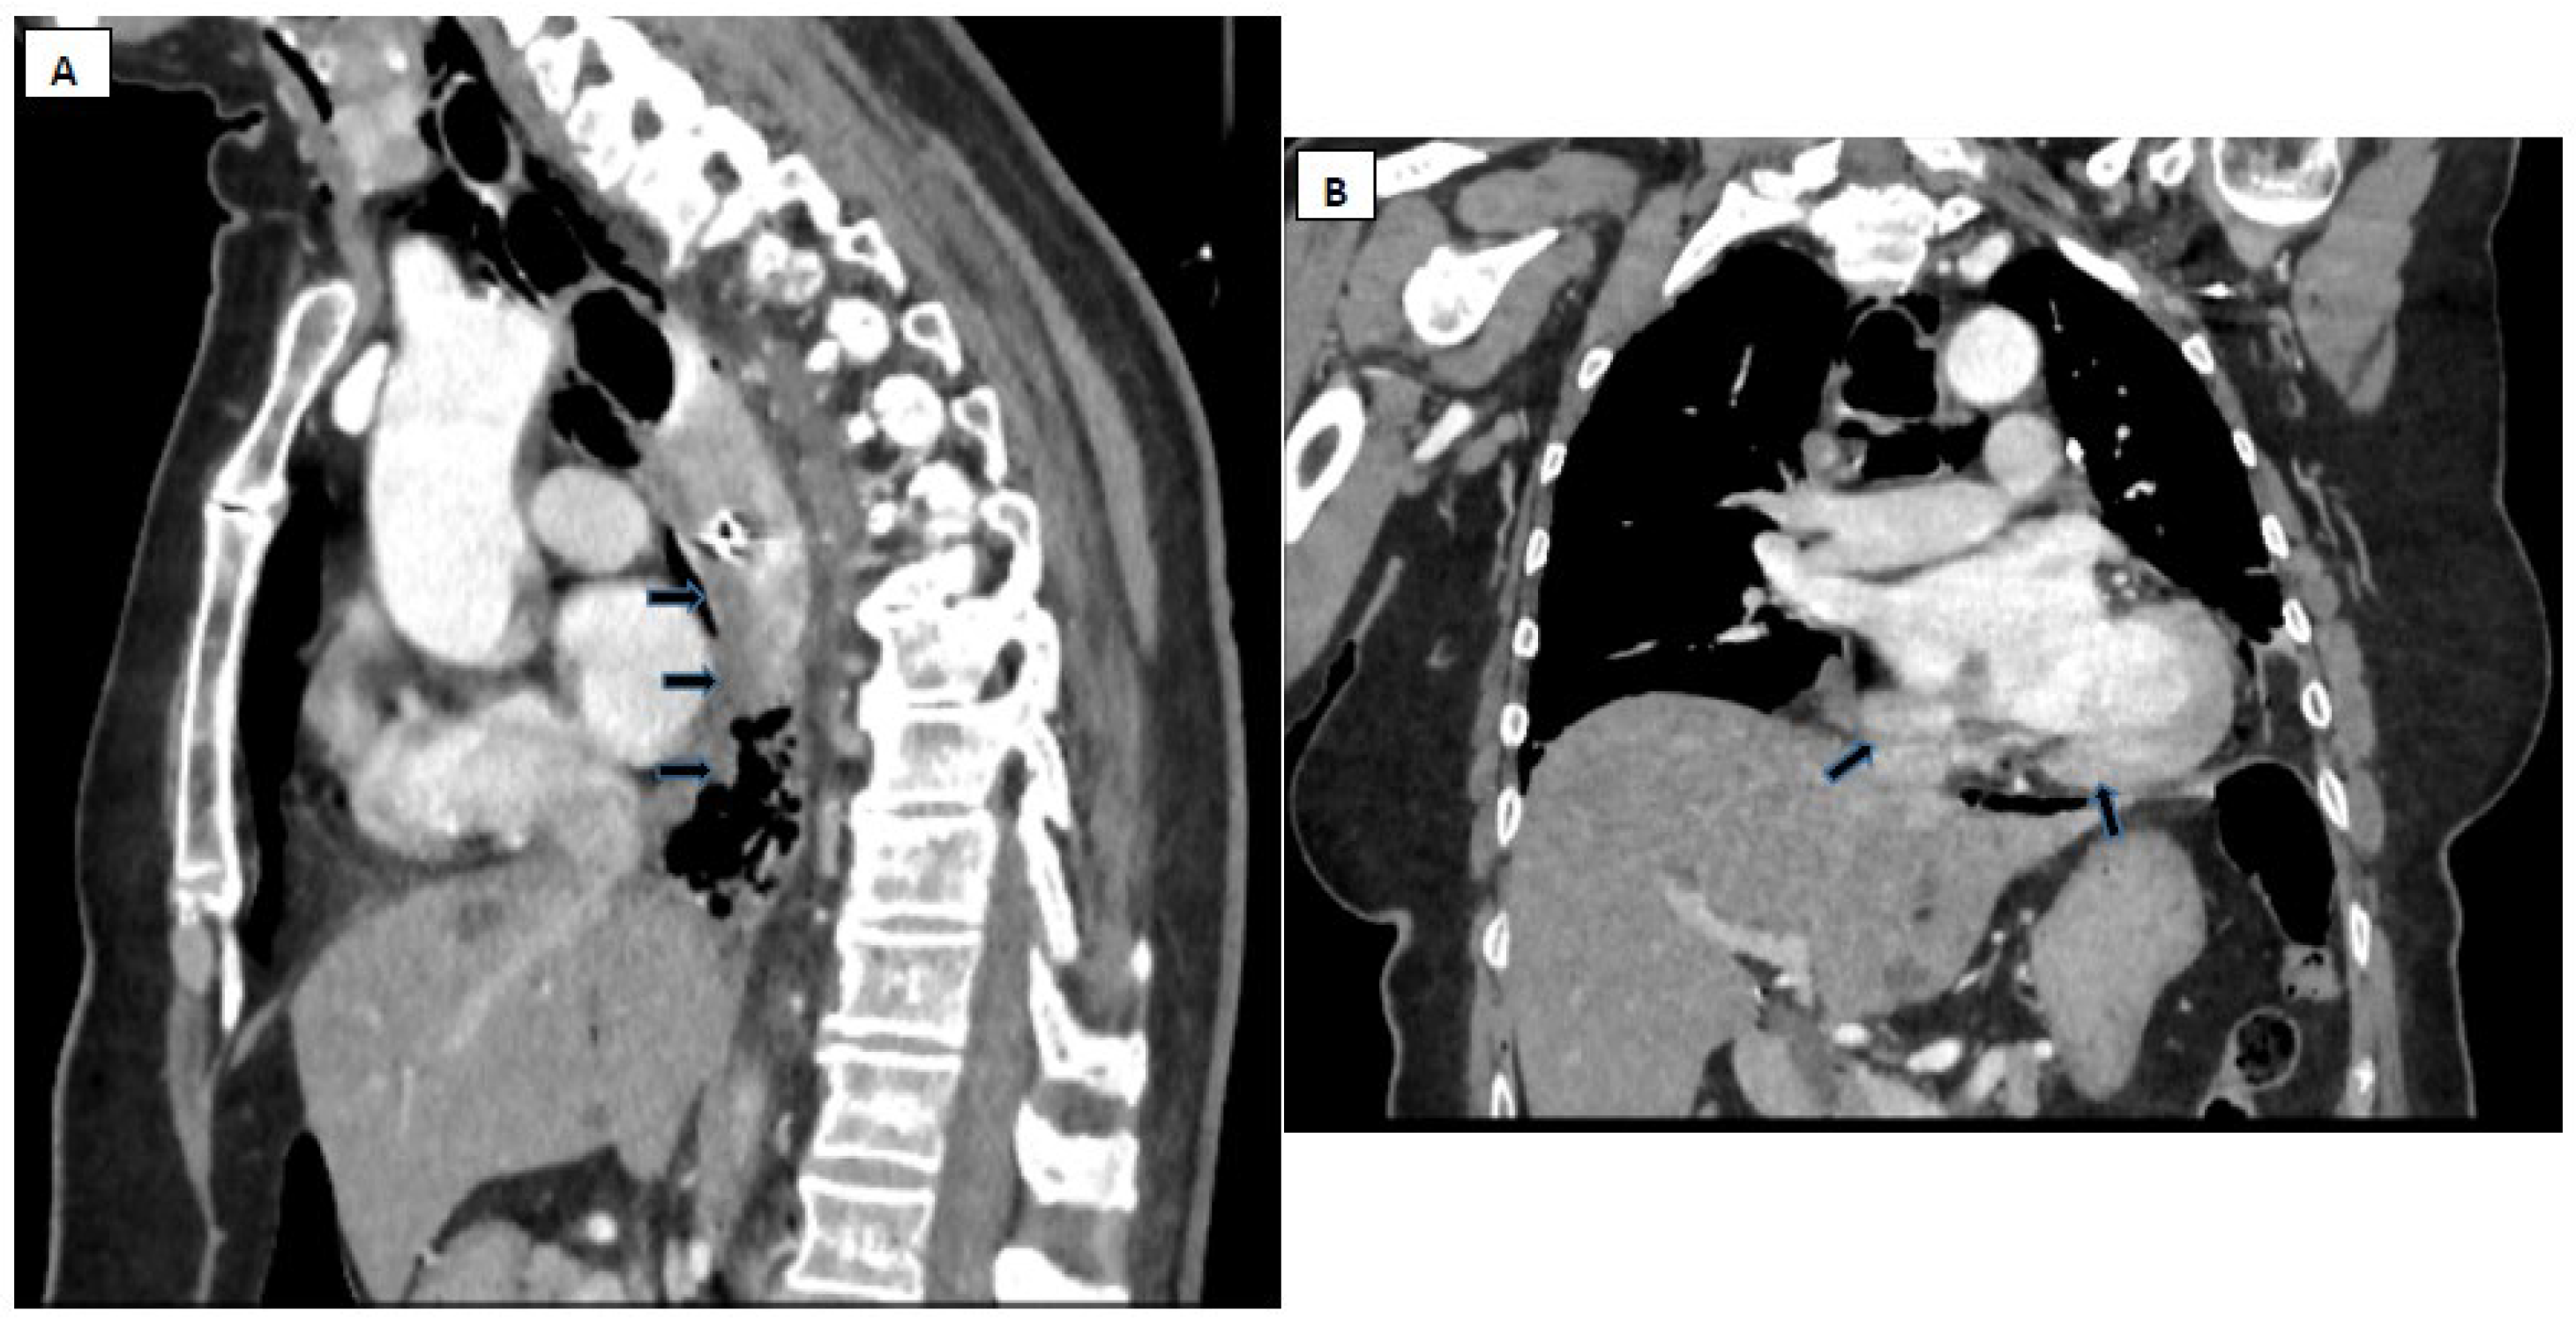

8. Paraclinical Investigations

- Pneumomediastinum

- Pneumothorax (especially left-sided)

- Pleural effusion (especially left-sided)

- Localized periaortic gas

- Mediastinal fluid collections

- Thickened esophageal wall

- Gas within thoracic soft tissues, neck, or around major vessels

- Gas in the epidural space

- Pneumoperitoneum

- Gas in the retroperitoneal space

- Oral contrast extravasation from the esophageal lumen [10].